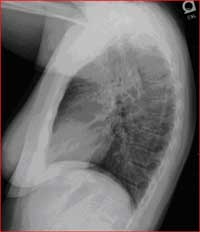

Normal Chest X-Ray